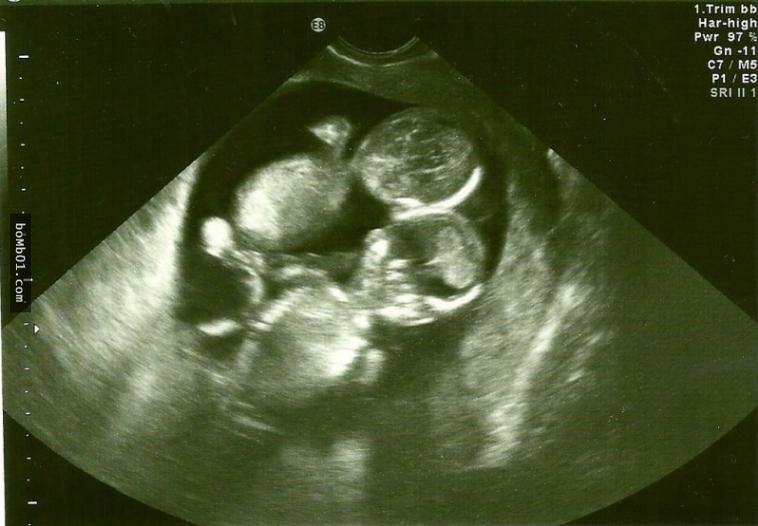

Kate và chồng đều rất yêu thích trẻ nhỏ nên đã nhận 2 đứa con nuôi. Tuy nhiên, Kate vẫn hy vọng có thể tự mình sinh con. Vì rất khó có con nên khi thấy mình có dấu hiệu mang thai, Kate vội tới bệnh viện kiểm tra, sau khi siêu âm, bác sĩ đã giơ hai ngón tay lên báo hiệu cô mang thai đôi. Thấy vậy, Kate vô cùng mừng rỡ.

Nhưng chưa vui mừng được bao lâu, Kate đã nhận được thông báo từ bác sĩ, thai nhi bị mắc hội chứng Monoamniotic. Đây là hội chứng xảy ra khi hai bào thai chia sẻ chung một túi ối không màng ngăn khiến dây rốn quấn quanh thai nhi trong quá trình phát triển. Điều này sẽ dẫn đến tình trạng thai thiếu oxy và chết lưu trong bụng mẹ. Xác xuất xảy ra hội chứng Monoamniotic này là 1% và tỷ lệ sống sót chỉ đạt 50%.

Bác sĩ đề nghị Kate không nên công khai tin cô có thai vì tình trạng thai nhi phát triển không tốt lắm. Nghe xong, Kate đã rất bàng hoàng, tuy nhiên cô vẫn ôm một tia hy vọng rằng hai bé sẽ bình an vô sự. Sau khi thai nhi được 28 tuần, cô bắt đầu nằm viện và lên kế hoạch mổ đẻ ở tuần 32.

Đến ngày sinh, Kate và gia đình vô cùng lo lắng. Nhưng khi tiến hành mổ đẻ, bác sĩ không khỏi kinh ngạc trước cảnh tượng: Dây rốn của cặp song sinh bị quấn vào nhau giống như tết tóc. Nhưng nó cũng không gây cản trở em bé hấp thu chất dinh dưỡng, hai bé gái đều ra đời thuận lợi.